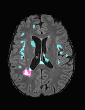

In recent years, data-driven machine learning (ML) methods have revolutionized the computer vision community by providing novel efficient solutions to many unsolved (medical) image analysis problems. However, due to the increasing privacy concerns and data fragmentation on many different sites, existing medical data are not fully utilized, thus limiting the potential of ML. Federated learning (FL) enables multiple parties to collaboratively train a ML model without exchanging local data. However, data heterogeneity (non-IID) among the distributed clients is yet a challenge. To this end, we propose a novel federated method, denoted Federated Disentanglement (FedDis), to disentangle the parameter space into shape and appearance, and only share the shape parameter with the clients. FedDis is based on the assumption that the anatomical structure in brain MRI images is similar across multiple institutions, and sharing the shape knowledge would be beneficial in anomaly detection. In this paper, we leverage healthy brain scans of 623 subjects from multiple sites with real data (OASIS, ADNI) in a privacy-preserving fashion to learn a model of normal anatomy, that allows to segment abnormal structures. We demonstrate a superior performance of FedDis on real pathological databases containing 109 subjects; two publicly available MS Lesions (MSLUB, MSISBI), and an in-house database with MS and Glioblastoma (MSI and GBI). FedDis achieved an average dice performance of 0.38, outperforming the state-of-the-art (SOTA) auto-encoder by 42% and the SOTA federated method by 11%. Further, we illustrate that FedDis learns a shape embedding that is orthogonal to the appearance and consistent under different intensity augmentations.